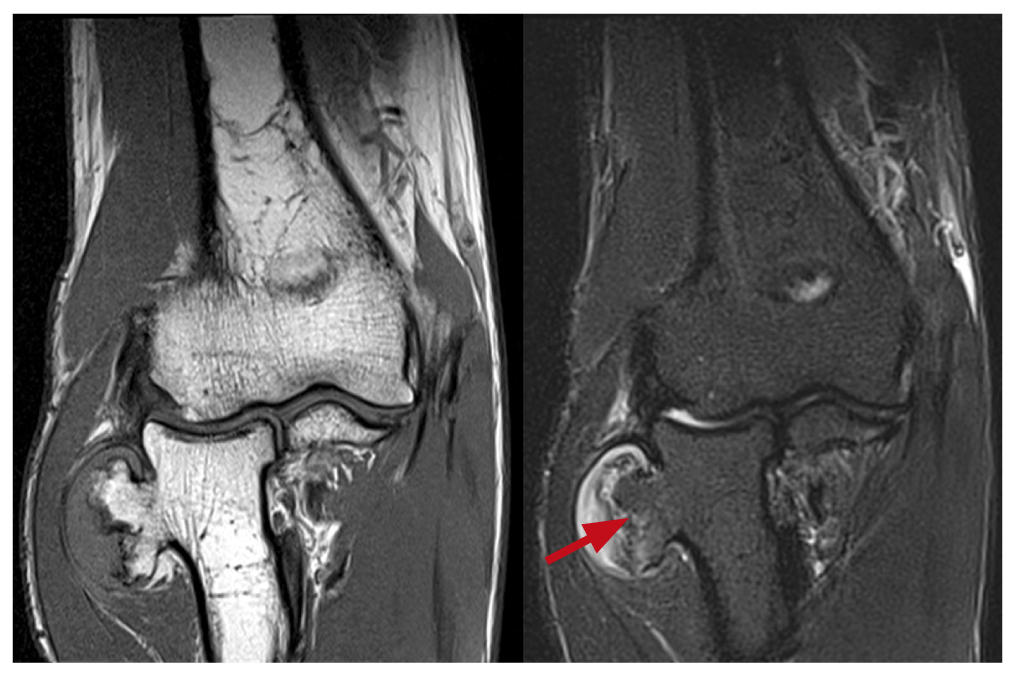

По результатам МРТ визуализирован хрящевой покров на верхушке новообразования (максимальная толщина 7 мм) и определено взаимоотношение с окружающими тканями; исключены признаки инфильтративного роста в области верхушки новообразования (рис. 4).

Рис. 4. Магнитно-резонансная томография левого локтевого сустава, фронтальная плоскость, Т1 и Т2 последовательности: красная линия указывает на толщину хрящевого покрова новообразования (7 мм)

Fig. 4. MRI of the left elbow joint, frontal plane, T1 and T2 sequences: the red line indicates the thickness of the cartilage covering the neoplasm (7 mm)